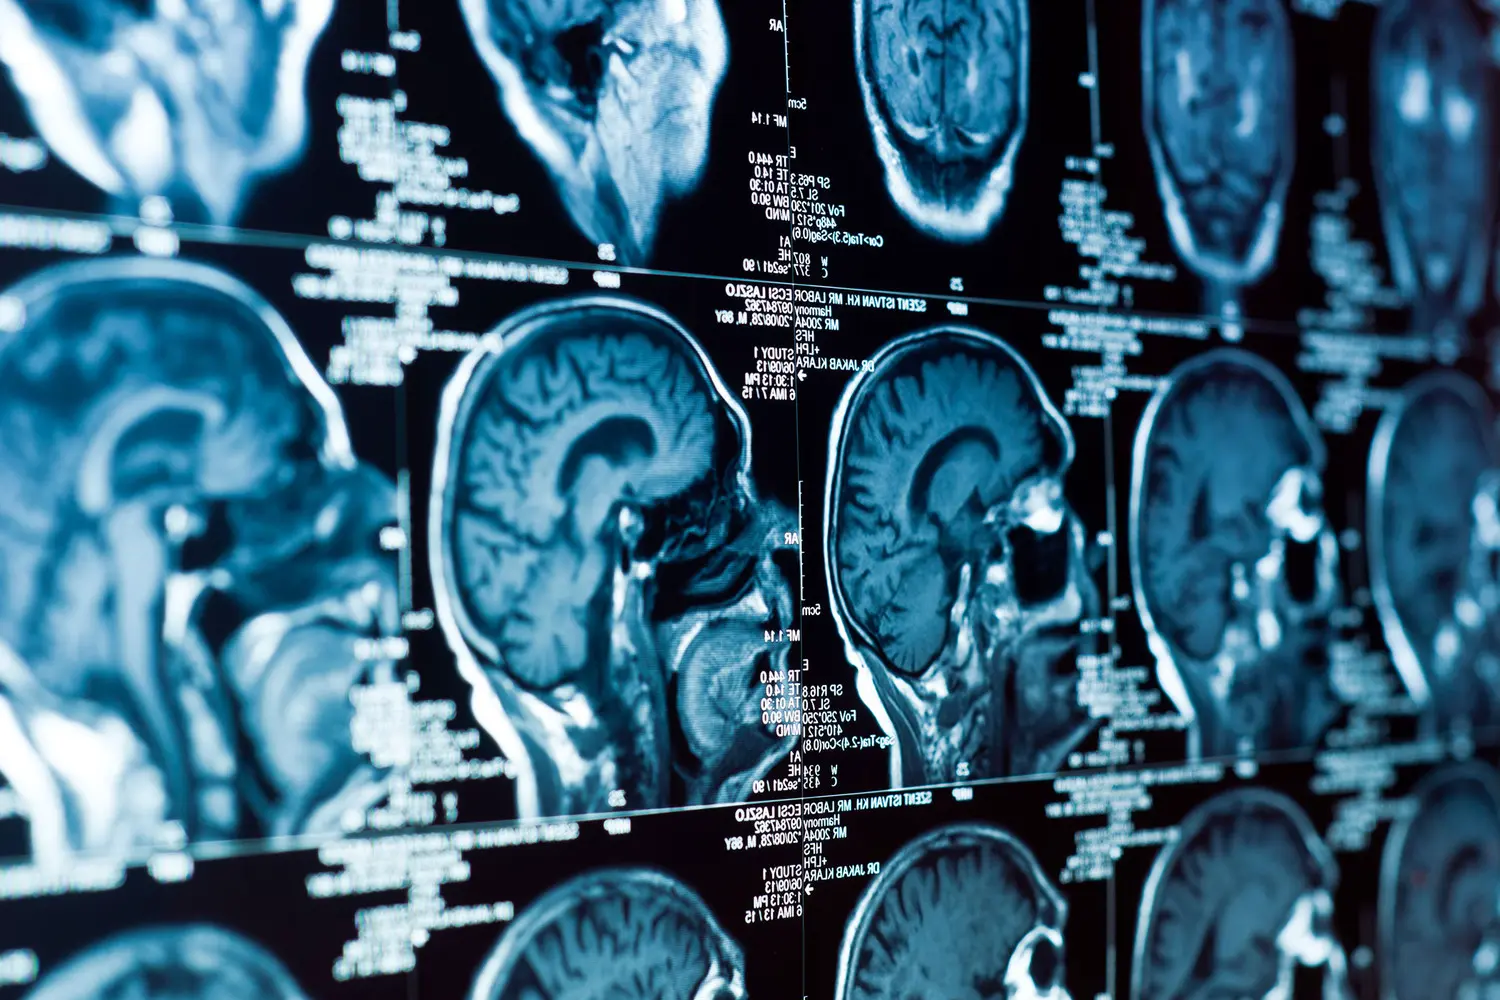

Диметилтриптамин (ДМТ) – психоактивное вещество, присутствующее в растениях и даже в организме человека – обнадеживающе проявило себя в восстановлении мозга после инсульта. Это важное открытие сделали ученые из Института биофизики HUN-REN BRC и Университета Земмельвайса в Венгрии.

Хотя ДМТ традиционно ассоциируется с ритуальными практиками, новые данные показывают его потрясающий потенциал для защиты от последствий ишемического инсульта. Лабораторные эксперименты на животных и клетках доказали: ДМТ эффективно снижает объем повреждений мозговой ткани, уменьшает отек и, что особенно важно, способствует регенерации гематоэнцефалического барьера — ключевой структуры на пути между кровью и нервными клетками.

Исследование выявило еще один замечательный эффект: ДМТ улучшает функциональное состояние астроглиальных клеток, активно участвующих в восстановлении нервных структур после повреждений. Вещество действует на специфические мозговые рецепторы, связанные с нейрозащитой. Одновременно оно подавляет деятельность провоспалительных молекул-цитокинов. Такой многогранный эффект делает ДМТ очень перспективным компонентом для дополнения существующих методов лечения инсульта.

Учитывая ограниченность текущих терапевтических подходов при инсульте, природное вещество, способное одновременно укреплять гематоэнцефалический барьер и бороться с воспалением, открывает захватывающие возможности. Как сообщают ученые, ДМТ уже проходит клинические испытания для оценки его безопасности и эффективности у людей. Есть большая надежда, что это соединение ляжет в основу создания прорывных нейропротекторных препаратов будущего.